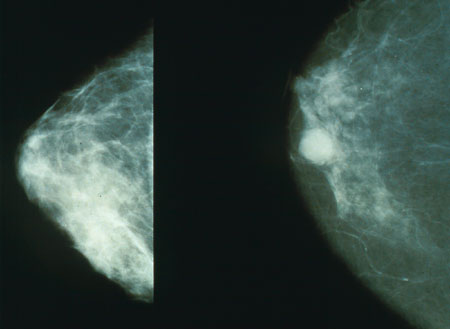

يوافق يوم 4 فبراير من كل عام اليوم العالمي للسرطان حيث تنضم منظمة الصحة العالمية إلى الاتحاد الدولي لمكافحة السرطان، وهو الجهة الراعية للاحتفالات بهذا اليوم، من أجل الترويج لسُبل التخفيف من العبء العالمي الناجم عن هذا المرض ؛ فالسرطان من أسباب الوفاة الرئيسية في جميع أنحاء العالم. وتشير تقديرات منظمة الصحة العالمية إلى أنّ هذا المرض يودي بحياة 8 مليون نسمة تقريبا سنويا . وأنقل للإخوة الزملاء تلك المقالة المفيدة عن هذاالموضوع الهام مرض السرطان ![]() (تبديد المفاهيم الخاطئة) السرطان مصطلح عام يشمل مجموعة من الأمراض يمكنها أن تصيب كل أجزاء الجسم، ويشار إلى تلك الأمراض أيضًا بالأورام. ومن السمات التي تميز السرطان التكاثر السريع لخلايا شاذة يمكنها النمو خارج حدودها المعروفة واقتحام أجزاء الجسد المتلاصقة والانتشار إلى أعضاء أخرى، ويطلق على تلك الظاهرة اسم (النقيلة). جدير بالذكر أن النقائل تمثل أهم أسباب الوفاة للسرطان. أسباب الإصابة بالسرطان: ينشأ السرطان من خلية واحدة. ويتم تحول الخلية الطبيعية إلى خلية سرطانية في مراحل متعددة، وعادة ما يتم ذلك التحول من آفة محتملة التسرطن إلى أورام خبيثة. وهذه التغيرات ناجمة عن التفاعل بين عوامل الفرد الجينية وبعض العوامل الخارجية. وتزيد نسبة الإصابة بالسرطان بشكل كبير مع التقدم في السن، ويعود ذلك - على الأرجح - إلى زيادة مخاطر الإصابة بسرطانات معينة مع التقدم بالعمر، وتراكم مخاطر الإصابة بالسرطان يتم إلى جانب انخفاض فعالية آليات الإصلاح الخلوي كلما تقدم الشخص في السن. جدير بالذكر أن تعاطي التبغ والكحول وقلة تناول الخضراوات والفاكهة والإصابة بفيروسي التهاب الكبد C وB والفيروس المسبب لسرطان عنق الرحم من عوامل الاختطار الرئيسة التي تقف وراء الإصابة بالسرطان في البلدان المنخفضة والمتوسطة الدخل. كما أن سرطان عنق الرحم الناجم عن فيروس الورم الحليمي البشري من أهم أسباب وفاة النساء جراء السرطان في البلدان المخفضة الدخل. ويمكن تلخيص أسباب الإصابة بالسرطان في التالي: تعاطي التبغ. فرط الوزن والسمنة. قلة تناول الخضراوات والفاكهة. الخمول البدني. تعاطي الكحول. أنواع العدوى المنقولة جنسيًا مثل العدوى بفيروس الإيدز والفيروس المسبب لسرطان عنق الرحم. تلوث الهواء في المدن المتقدمة. التعرض للدخان الناجم عن حرق الوقود الصلب داخل المباني. عوامل الخطورة: العمر: معظم حالات السرطان تكتشف عند سن 55 وأكبر، إلا أن السرطان ممكن أن يكتشف عند أية مرحلة عمرية. نمط الحياة: يزيد معدل السرطان لدى الأشخاص ذوي السلوكيات غير الصحية كالتدخين وشرب الكحول والتعرض المباشر لأشعة الشمس والعلاقات المحرمة. التاريخ العائلي: تتحمل الوراثة 5-10% من نسبة الإصابة بالسرطان ولكن ليس بالضرورة أن كل من لديه عامل وراثي يصاب بالسرطان. الحالة الصحية: هناك علاقة بين الأمراض المزمنة والسرطان مثل مرض التهاب القولون المزمن. الأعراض والعلامات: تختلف الأعراض حسب العضو المصاب في الجسم ما بين حمى، وألم، وشعور بالتعب والإرهاق، وتغير مفاجئ في الوزن (نقص في الغالب). كما تظهر كتلة أو سمك محسوس تحت الجلد، ويتغير لون الجلد (اصفرار، احمرار، التحول إلى اللون الداكن) أو وجود جروح لا تلتئم، كحة مستمرة، بحة في الصوت، صعوبة في البلع، عسر في الهضم، تغير في عادة التبرز والإخراج. التشخيص: قد يجري الطبيب أحد الإجراءات التالية لتشخيص المرض حسب حالة المريض وهي: الفحص السريري: يفحص الطبيب جسم المريض ويبحث عن أي كتلة أو تغير في لون الجلد أو زيادة في الحجم تدل على حدوث السرطان. فحوصات المختبر: ويتم ذلك بأخذ عينة من الدم للكشف عن السرطان مثل سرطان الدم. الأشعة: تعمل الأشعة على فحص العظام والأعضاء الداخلية مثل الأشعة الصوتية، وأشعة العظام، والتصوير بالرنين المغناطيسي، والأشعة المقطعية. الخزعة: هناك طرق مختلفة لجمع عينة الخزعة، ويعتمد أخذ الخزعة على نوع السرطان وموقعه في الجسم. وفي معظم حالات السرطان يكون أفضل طريقة لتشخيص المرض وأضمنها. يساعد تشخيص السرطان في مرحلة مبكرة على سرعة علاج الحالة ومن ثم الشفاء - بإذن الله. يساعد الفحص الطبي الدوري على اكتشاف السرطان في مرحلة مبكرة. ويجرى بصورة منتظمة للفئات الأكثر عرضة للإصابة بالمرض. أوصت الجمعية الأمريكية للسرطان بمجموعة فحوصات طبية تجرى للوقاية من السرطان للبالغين. الفئات الأكثر عرضــــــــــــــــــــــة نوع السرطــــــــــــان النساء عند عمر 40 سنة أو أكبر  سرطان الثدي النساء عند عمر 21 أو أكبر سرطان عنق الرحم النساء والرجال عند عمر 50 سنة أو أكبر سرطان القولون الرجال عند عمر 50 سنة أو أكبر سرطان البروستاتا مراحل الإصابة بالسرطان: يبحث الطبيب عن مراحل انتشار المرض في الجسم، وبصفة عامة يصنف السرطان بأربع مراحل تبدأ من (المرحلة الأولى) إلى (المرحلة الرابعة) وتعد المرحلة الرابعة الأشد خطورة. مضاعفات السرطان: التفاعل غير الطبيعي للجهاز المناعي مع السرطان: في بعض الحالات يتفاعل الجهاز المناعي ويهاجم الخلايا السليمة. انتشار المرض: قد يهاجم السرطان أجزاء أخرى من الجسم. وغالبًا يمكن التحكم به لكن لا يمكن علاجه. عودة المرض مرة أخرى: بعض أنواع السرطان من الممكن أن يعاود الظهور مرة أخرى، لذلك من المهم متابعة الحالة بعد العلاج وعمل الفحوصات الطبية الدورية. العلاج: يعتمد علاج السرطان على عدة عوامل لعل أبرزها نوع السرطان ومرحلته وحالة المريض الصحية. الغرض من علاج السرطان: العلاج الأولي: ويتم عادة عن طريق الجراحة بغرض التخلص من الخلايا السرطانية. العلاج المساند: يعمل على قتل الخلايا السرطانية المتبقية بعد العلاج الأولي كالعلاج الكيميائي أو الإشعاعي أو الهرموني. العلاج التلطيفي: وهو العلاج بغرض التحكم في مضاعفات المرض. خيارات علاج السرطان: العلاج الجراحي: للتخلص من الورم. العلاج الكيمائي: وهي أدوية تعمل على قتل الخلايا السرطانية. العلاج الإشعاعي: باستخدام أشعة عالية الطاقة مثل أشعة إكس. زراعة خلايا الجذع: وذلك بوساطة نقل نخاع العظم ويمكن أن يؤخذ من المريض أو من متبرع. العلاج البيولوجي: يساعد الجهاز المناعي للجسم على الكشف عن الخلايا السرطانية ومحاربتها. العلاج الهرموني: بعض أنواع السرطان تتغذى على هرمونات الجسم مثل سرطان الثدي والبروستاتا، فعند التخلص من هرمون الجسم تموت الخلية السرطانية. الوقاية: لا توجد طريقة محددة للوقاية من السرطان لكن هناك عوامل تقلل من خطورة المرض وهي كالتالي: امتنع عن التدخين: فهناك علاقة قوية بين السرطان والتدخين، خصوصًا سرطان الرئة. تجنب التعرض المباشر للأشعة، خصوصًا الأشعة فوق البنفسجية الضارة وذلك بالجلوس في الظل، وارتداء الملابس الواقية واستخدام كريم واقٍ من أشعة الشمس. التغذية السليمة: باختيار الأغذية الغنية بالفاكهة والخضراوات واختيار الحبوب الكاملة كالشوفان والأرز البني والقمح المجروش. مارس الرياضة بانتظام: ممارسة الرياضة لمدة 30 دقيقة يوميًا تساعد على تقليل فرصة حدوث السرطان. حافظ على الوزن المثالي: أثبتت الأبحاث أن هناك علاقة وطيدة بين السمنة (زيادة الوزن) والسرطان، ويمكن الوصول إلى الوزن المثالي بالرياضة المنتظمة والتغذية السليمة. إجراء الفحص الطبي بانتظام. التطعيمات: توجد فيروسات محددة تسبب السرطان مثل فيروس التهاب الكبدي الوبائي (ب) الذي يسبب سرطان الكبد والفيروس المسبب لسرطان عنق الرحم، وبإمكان التطعيم أن يقيك - بإذن الله - من هذه الفيروسات. خذ قسطًا كافيًا من النوم والراحة. تجنب ضغوط الحياة ومارس هواياتك. المصدر http://www.moh.gov.sa/HealthAwarenes...01-18-001.aspx التعديل الأخير تم بواسطة أحمد صلاح الحفني ; 2014-02-04 الساعة 01:44 PM.  |